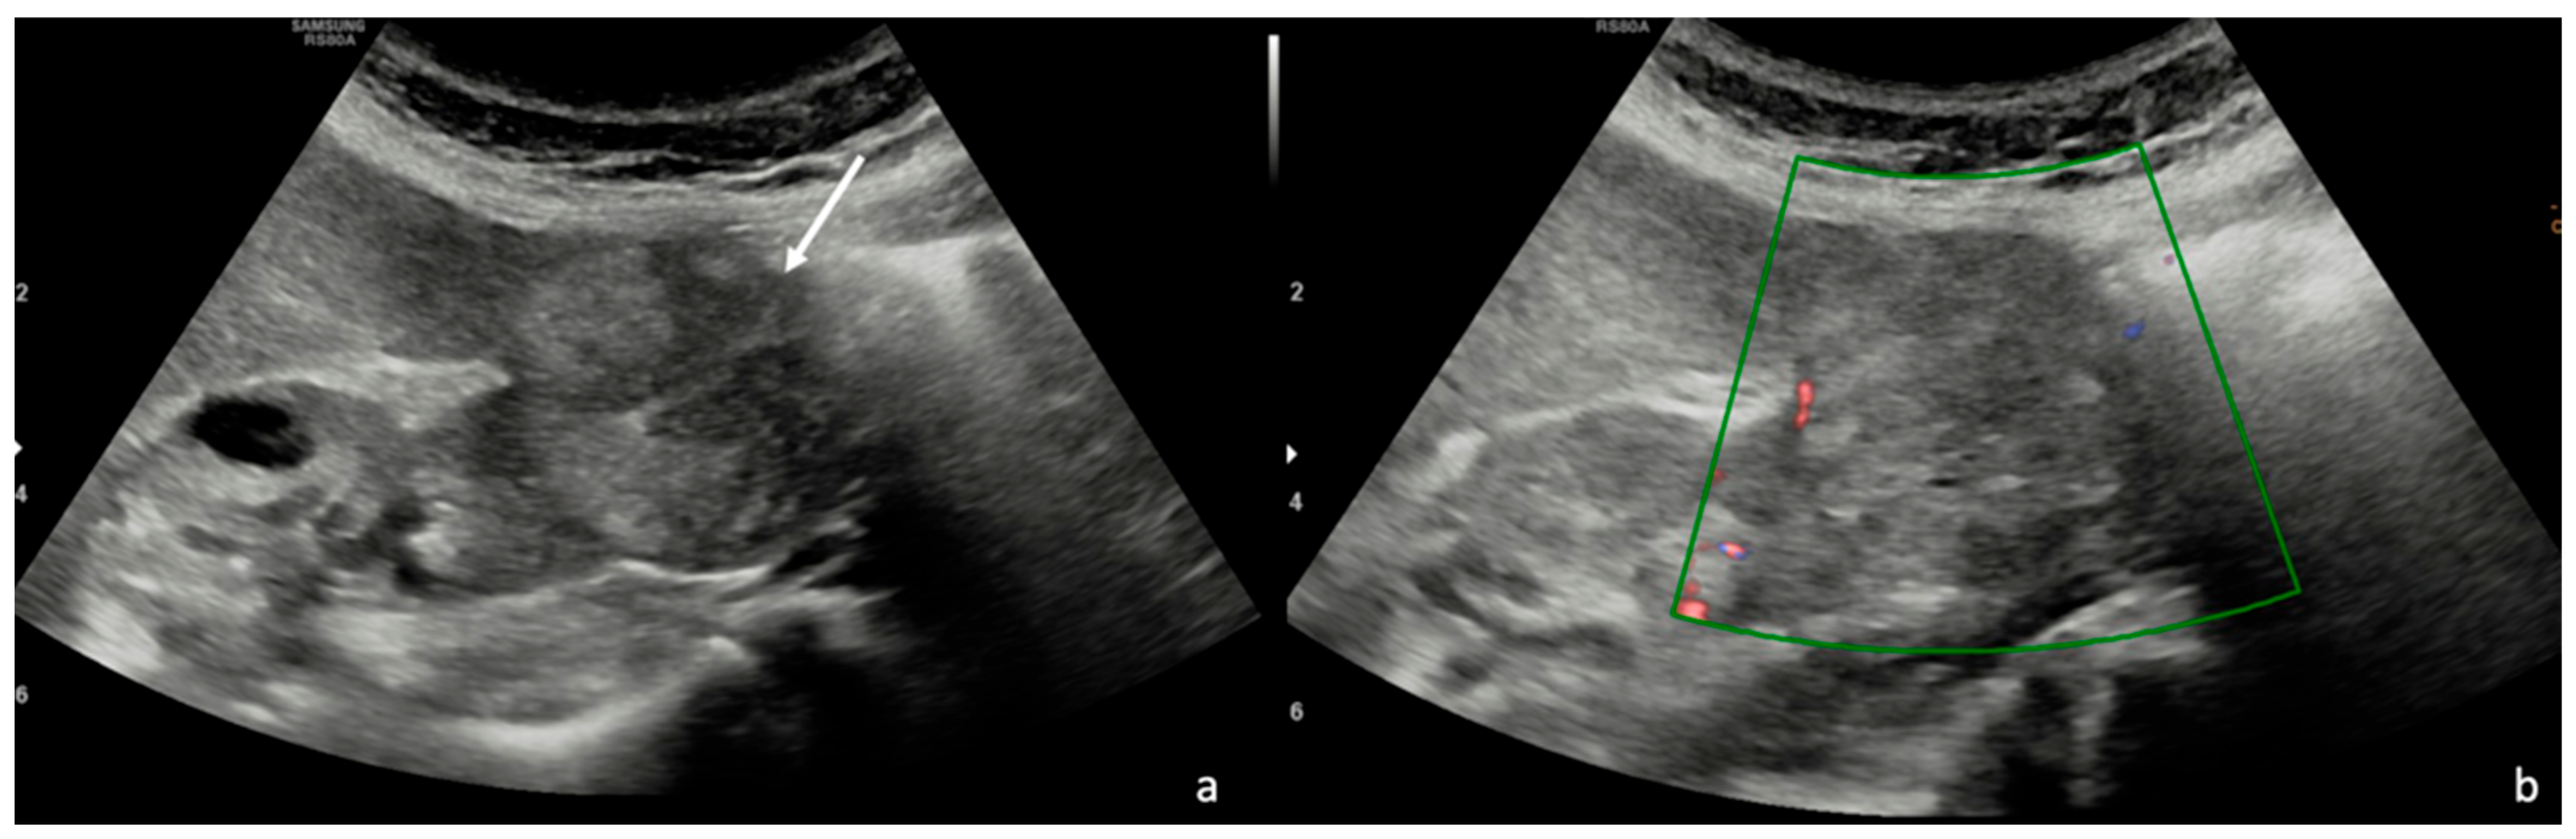

3.1. Ultrasound (US)

3.2. Contrast-Enhanced Ultrasound (CEUS)